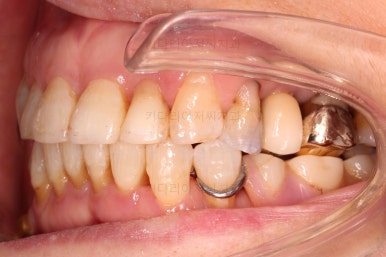

초진 시 입안의 모습입니다.

일반적인 교정을 하기에는 적합한 모습은 아니었어요.

치아는 군데군데 없고 임플란트도 있고 브릿지로 연결된 치아도 있으며 전반적인 잇몸 상태도 좋지 못했어요.

앞니가 벌어져 있고 뻗쳐 있으며 잇몸에서 쏙 빠져나와 있는 듯한 느낌이었어요.